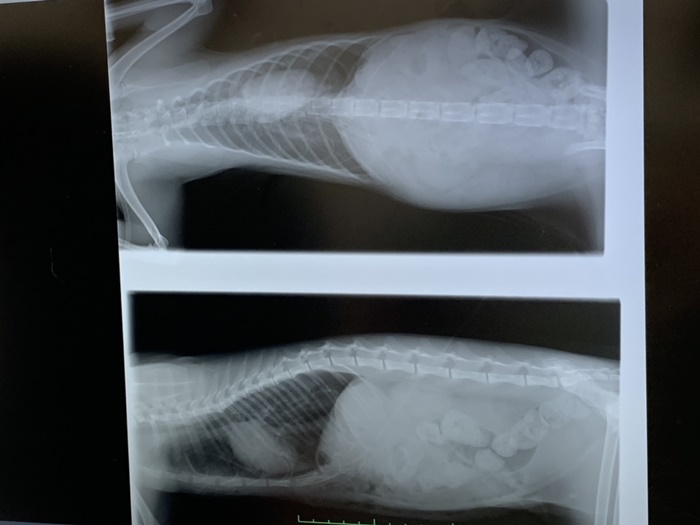

胃と肺が癒着、横隔膜と肝臓が癒着、 ゆっくりと剥がしながら

進められました。

ミケコちゃんのお腹には赤ちゃんが!

赤ちゃんは6匹 。まだ2週〜3週くらいの小さな卵胞 。

手術は成功していますが

問題なのはまだ自発呼吸が少し弱く

酸素濃度が少ないこと。

酸素不足で脳に障害が出ないよう

今は酸素室です。